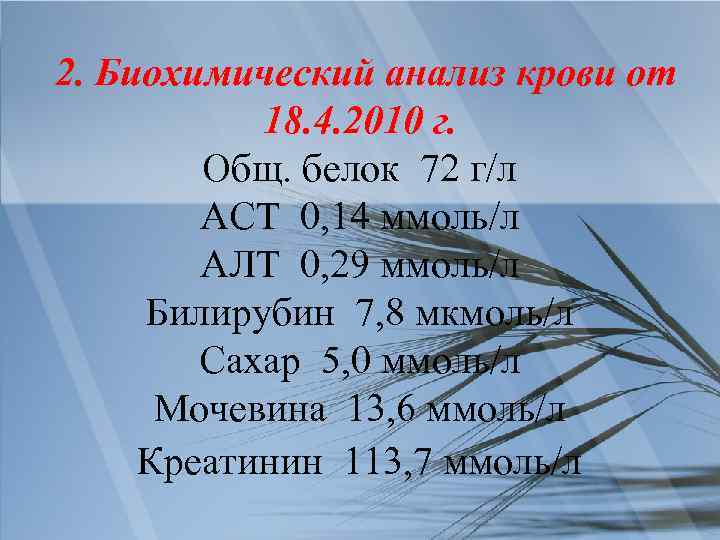

2. Биохимический анализ крови от 18. 4. 2010 г. Общ. белок 72 г/л АСТ 0, 14 ммоль/л АЛТ 0, 29 ммоль/л Билирубин 7, 8 мкмоль/л Сахар 5, 0 ммоль/л Мочевина 13, 6 ммоль/л Креатинин 113, 7 ммоль/л